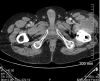

Description:Tularemia is a zoonotic infection caused by Francisella tularensis. Its most typical manifestations in humans are ulceroglandular and glandular; infections in prosthetic joints are rare. We report 3 cases of F. tularensis subspecies holarctica-related prosthetic joint infection that occurred in France during 2016-2019. We also reviewed relevant literature and found only 5 other cases of Francisella-related prosthetic joint infections worldwide, which we summarized. Among those 8 patients, clinical symptoms appeared 7 days to 19 years after the joint placement and were nonspecific to tularemia. Although positive cultures are typically obtained in only 10% of tularemia cases, strains grew in all 8 of the patients. F. tularensis was initially identified in 2 patients by matrix-assisted laser desorption/ionization time-of-flight mass spectrometry; molecular methods were used for 6 patients. Surgical treatment in conjunction with long-term antimicrobial treatment resulted in favorable outcomes; no relapses were seen after 6 months of follow-up.